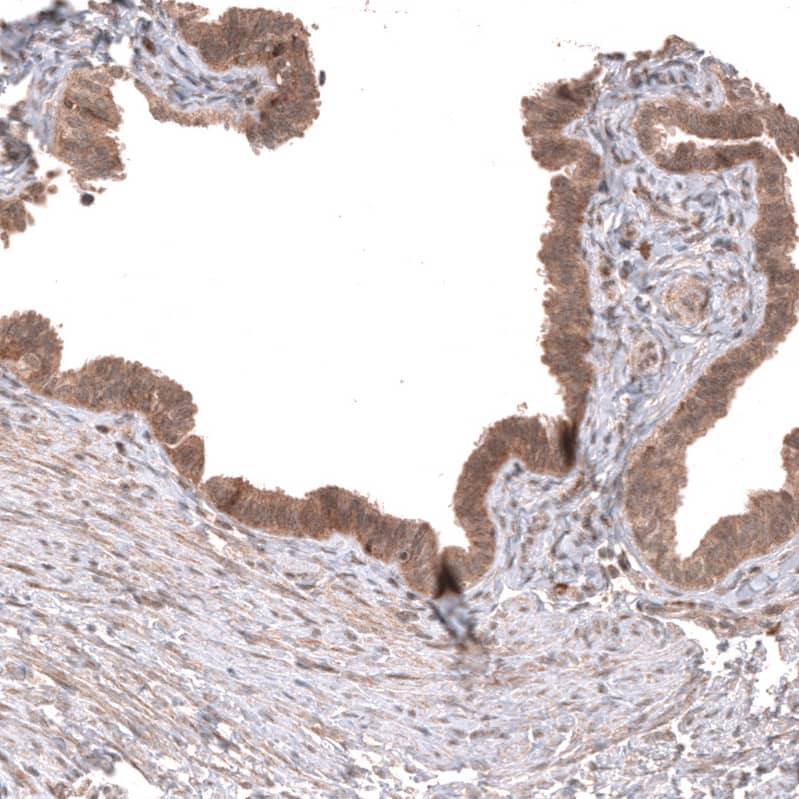

Staining of human fallopian tube shows moderate cytoplasmic positivity in glandular cells.